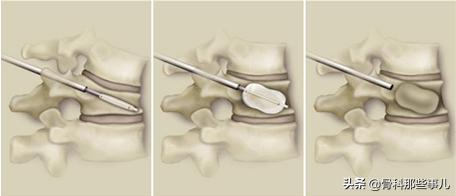

按照前面讲的3种建议手术的情况,第①种和第②种情况可以做微创的椎体成形术(英文首字母缩写PVP)或者椎体后凸成形术(应为首字母缩写为PKP)。大致原理是通过透视,直接从背部的皮肤,用一根穿刺针穿入骨折的椎体,向椎体内注射一种称为“骨水泥”的材料。这种材料大约15~20分钟即可完全硬化,对受伤的椎体起到支撑的作用,并且有很不错的镇痛效果。

PVP手术的示意图,通过向受伤的椎体内注入“骨水泥”,快速支撑和镇痛

如果椎体压缩比较明显,则需要先使用一个球囊把椎体撑起来,然后退出球囊,再注射骨水泥,这种做法称为PKP。

相比于PVP手术,PKP则多一个用球囊撑起压缩椎体的过程